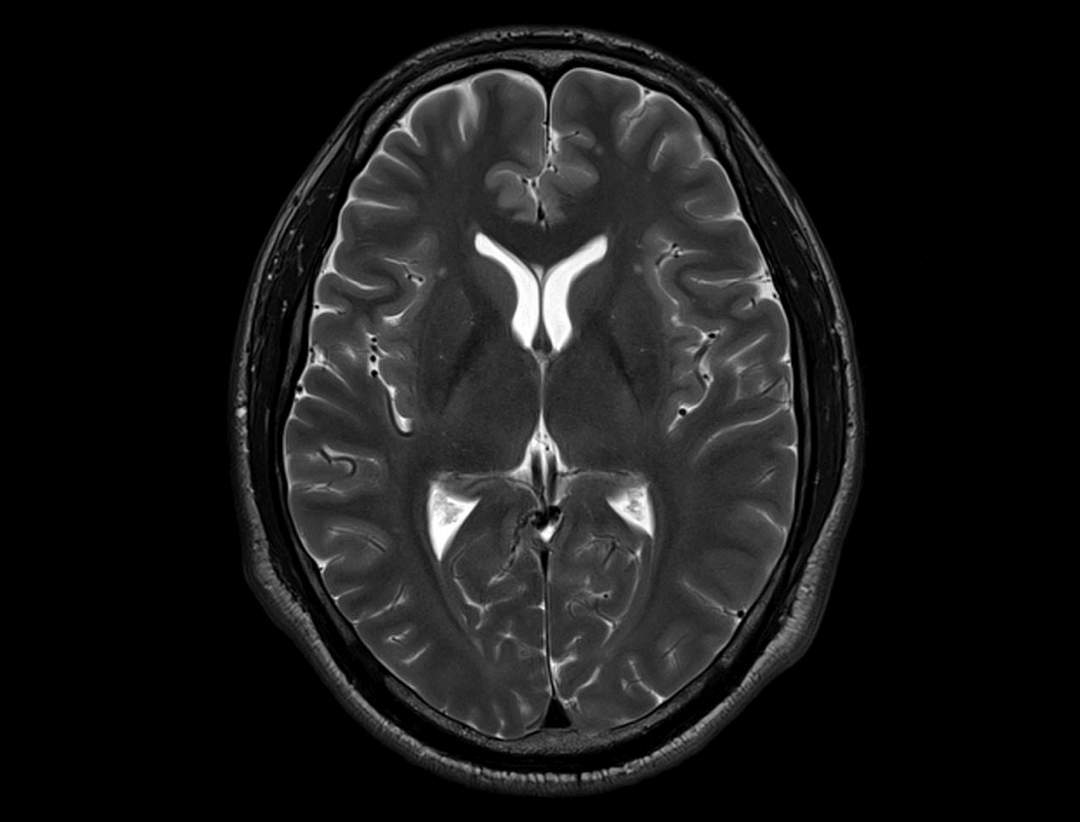

uMR® 770 provides high-speed imaging on all anatomy with significant scan time reduction.

Acceleration technology enables the uMR® 770 to significantly improve scan efficiency and increase patient throughput.